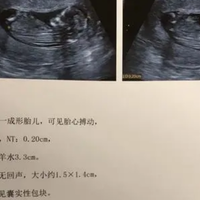

因为NT检查通常在怀孕11-14周进行,此时胎儿的颈部透明层最易测量,而且怀孕7周时,胎儿尚未发育完全,此时检查会影响结果的准确性,相比之下,大家的血液hCG检查和孕酮值等其他检查更为关键,这些检查会更加有助于监测胎儿和孕妇的健康状况,所以大家可以先不用着急做这项检查。NT检查主要是指针对胎儿的发育情况进行彩超检查,它可以检测胎儿的颈部透明层的厚度,诊断染色体疾病或者是其他疾病造成的胎儿畸形,对于

因为NT检查通常在怀孕11-14周进行,此时胎儿的颈部透明层最易测量,而且怀孕7周时,胎儿尚未发育完全,此时检查会影响结果的准确性,相比之下,大家的血液hCG检查和孕酮值等其他检查更为关键,这些检查会更加有助于监测胎儿和孕妇的健康状况,所以大家可以先不用着急做这项检查。NT检查主要是指针对胎儿的发育情况进行彩超检查,它可以检测胎儿的颈部透明层的厚度,诊断染色体疾病或者是其他疾病造成的胎儿畸形,对于

怀孕11周的nt值1.1mm在正常范围内。正常女性怀孕11周-12周的NT正常值为小于3mm,1.1mm属于正常值,不必过于担心。NT值是指由胎儿颈部后方超声波测量而得出的一项指标,是评估胎儿是否有染色体异常和某些畸形的重要指标之一。这个颈部透明带的厚度只要不超过3mm,就证明染色体不存在异常。因此怀孕11周nt检查结果1.1mm是正常的,孕妇不必担心,安心养胎就好。NT值是指通过超声波测量胎儿颈